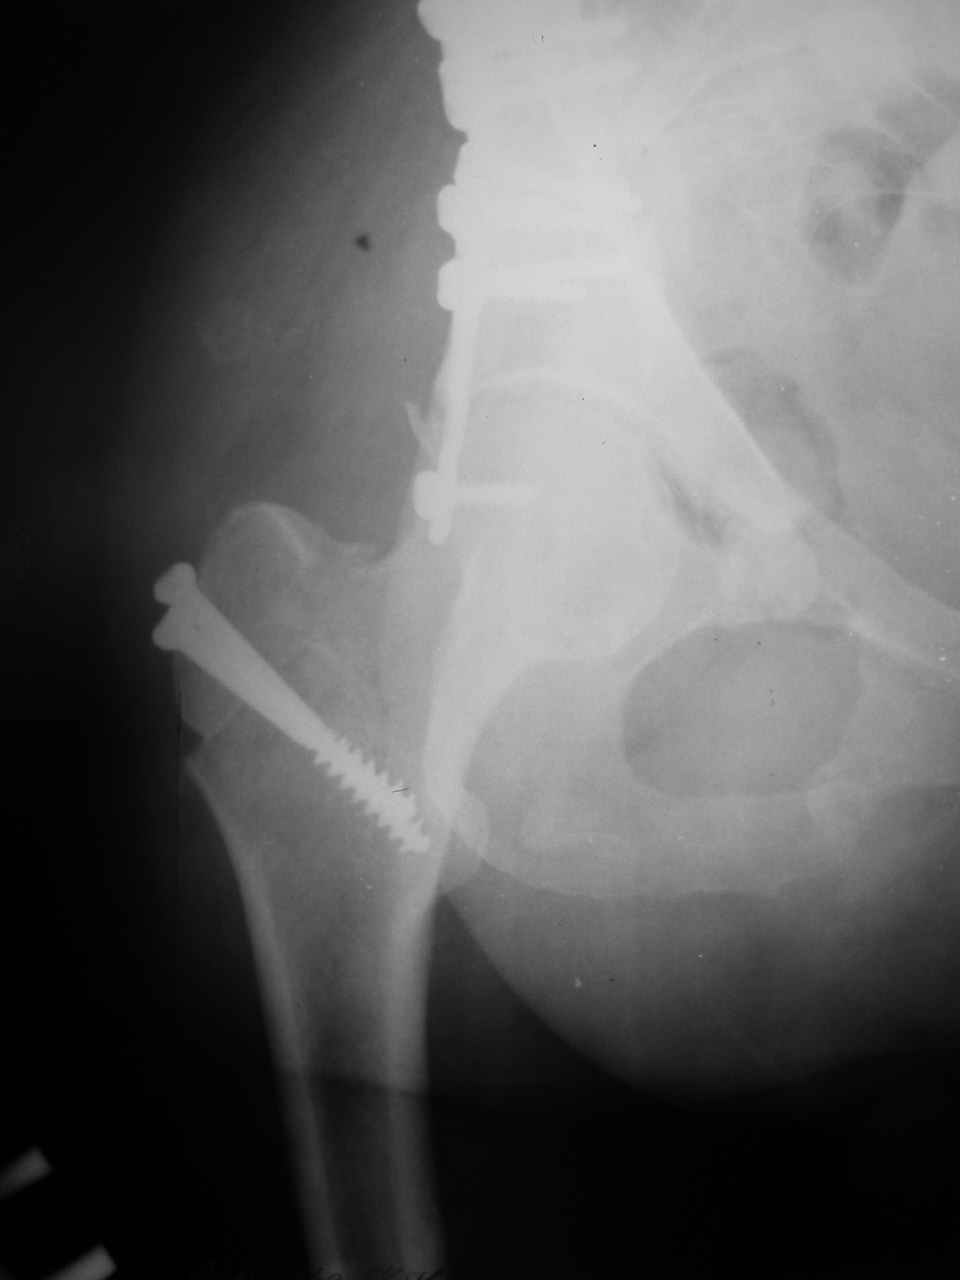

А какой отдел вертлужной впадины более важен передний или задний? Чем был обусловлен выбор доступа к суставу? Проще говоря, почему вы пошли передним доступом на двухколонный перелом? Мне понятны ваши сомнения, когда не удется сделать все что хотелось бы. В данном случае доступ должен быть чрезвертельным боковым (как и советовал Рунков) или двумя доступами.

Интерес к реконструкции вертлужной впадины у меня появился довольно-таки давно, но до недавнего времени как-то не ощущалась готовность к практической реализации, а местный подход достаточно консервативен - перелом срастется,

а далее будет видно. Такую точку зрения я не разделяю, поэтому через конференции,ортофорум и свои случаи пытаюсь практически и теоретически *продвинуть* для себя тему реконструкции вертлужной впадины.

Логика подсказывает, что все-таки лучше иметь анатомически полноценную впадину, хотя ранее упоминалось состояние вторичной конгруэнтности и одно наблюдение у меня есть, когда у больного с полностью нарушенной анатомией впадины и подвывихом головки бедра кзади и кверху боли отсутствовали при относительно достаточном для стиля жизни больного объёме движений. Но это только одно наблюдение и кроме перелома впадины у этогобольного была и тяжелая ЧМТ в анамнезе. Основываясь на формулировке структуры ацетабулюм Э. Летурнеля - как перевернутой буквы Y, впадина для полноценной функции сустава должна иметь сферичность, соответствующую размеру головки бедра и если один из компонентов в дефиците, то функциональные последствия рано или поздно проявятся.

Сложностью, ассоциативностью характера перелома, я бы с радостью воспользовался мининвазивной перкутанной фиксацией винтами, но боюсь, что результат был бы ещё хуже, техникой непрямой репозиции перелома не владею, поэтому пытаясь получить анатомичную впадину приходится широко открывать, по крайней мере пока, а дальше буду пытаться уменьшать пространство...

> передним доступом на двухколонный перелом?

Илеофеморальный доступ не совсем передний и сравнительно с илеоингвинальным, и Кохера-Лангенбека открывает весь наружный таз кроме самых передних отделов лонных костей, фиксацию которых я не ставил в задачу. Обширность диссекции, большая длительность операции и более высокий риск гетерооссификации - отрицательные моменты в обмен на возможность легче ориентироваться.

Вопрос доступа к вертлужной впадине при остеосинтезе задача не простая. Конечно, у Летурнеля и Тайла всё давно описано, нам остается только брать на вооружение. Но сами понимаете, что не бывает двух одинаковых ситуаций, поэтому в каждом случае вопрос решается сугубо индивидуально. Наша главная цель - восстановить анатомию с нанесением минимальной дополнительной травмы тазобедреннному суставу, думаю с этим никто не поспорит. Расширенный илиофеморальный доступ уж слишком травматичен (как сказал один коллега "таз лежит отдельно, больной отдельно").Стоит ли делать из пациента анатомический препарат для того чтобы легче ориентироваться. Да и нужно ли собирать всю "мозаику"? Мы применяли при таких операциях своеобразную операционную хитрость - сначала устраняли грубое смещение крыла под гребнем с фиксацией так называемой "плавающей" пластиной (временно фиксированной на двух винтах)- доступ или продлевали боковой, или делали небольшой дополнительный разрез над гребнем. Это позволяло устранить грубое смещение и захождение отломков тела повздошной кости, что значительно облегчало репозицию и остеосинтез впадины над сводом. Основное внимание конечно же уделяли нагружаемому задне-верхнему отделу. Сообщите ваш адрес, пришлю схемы и рентгенограммы.